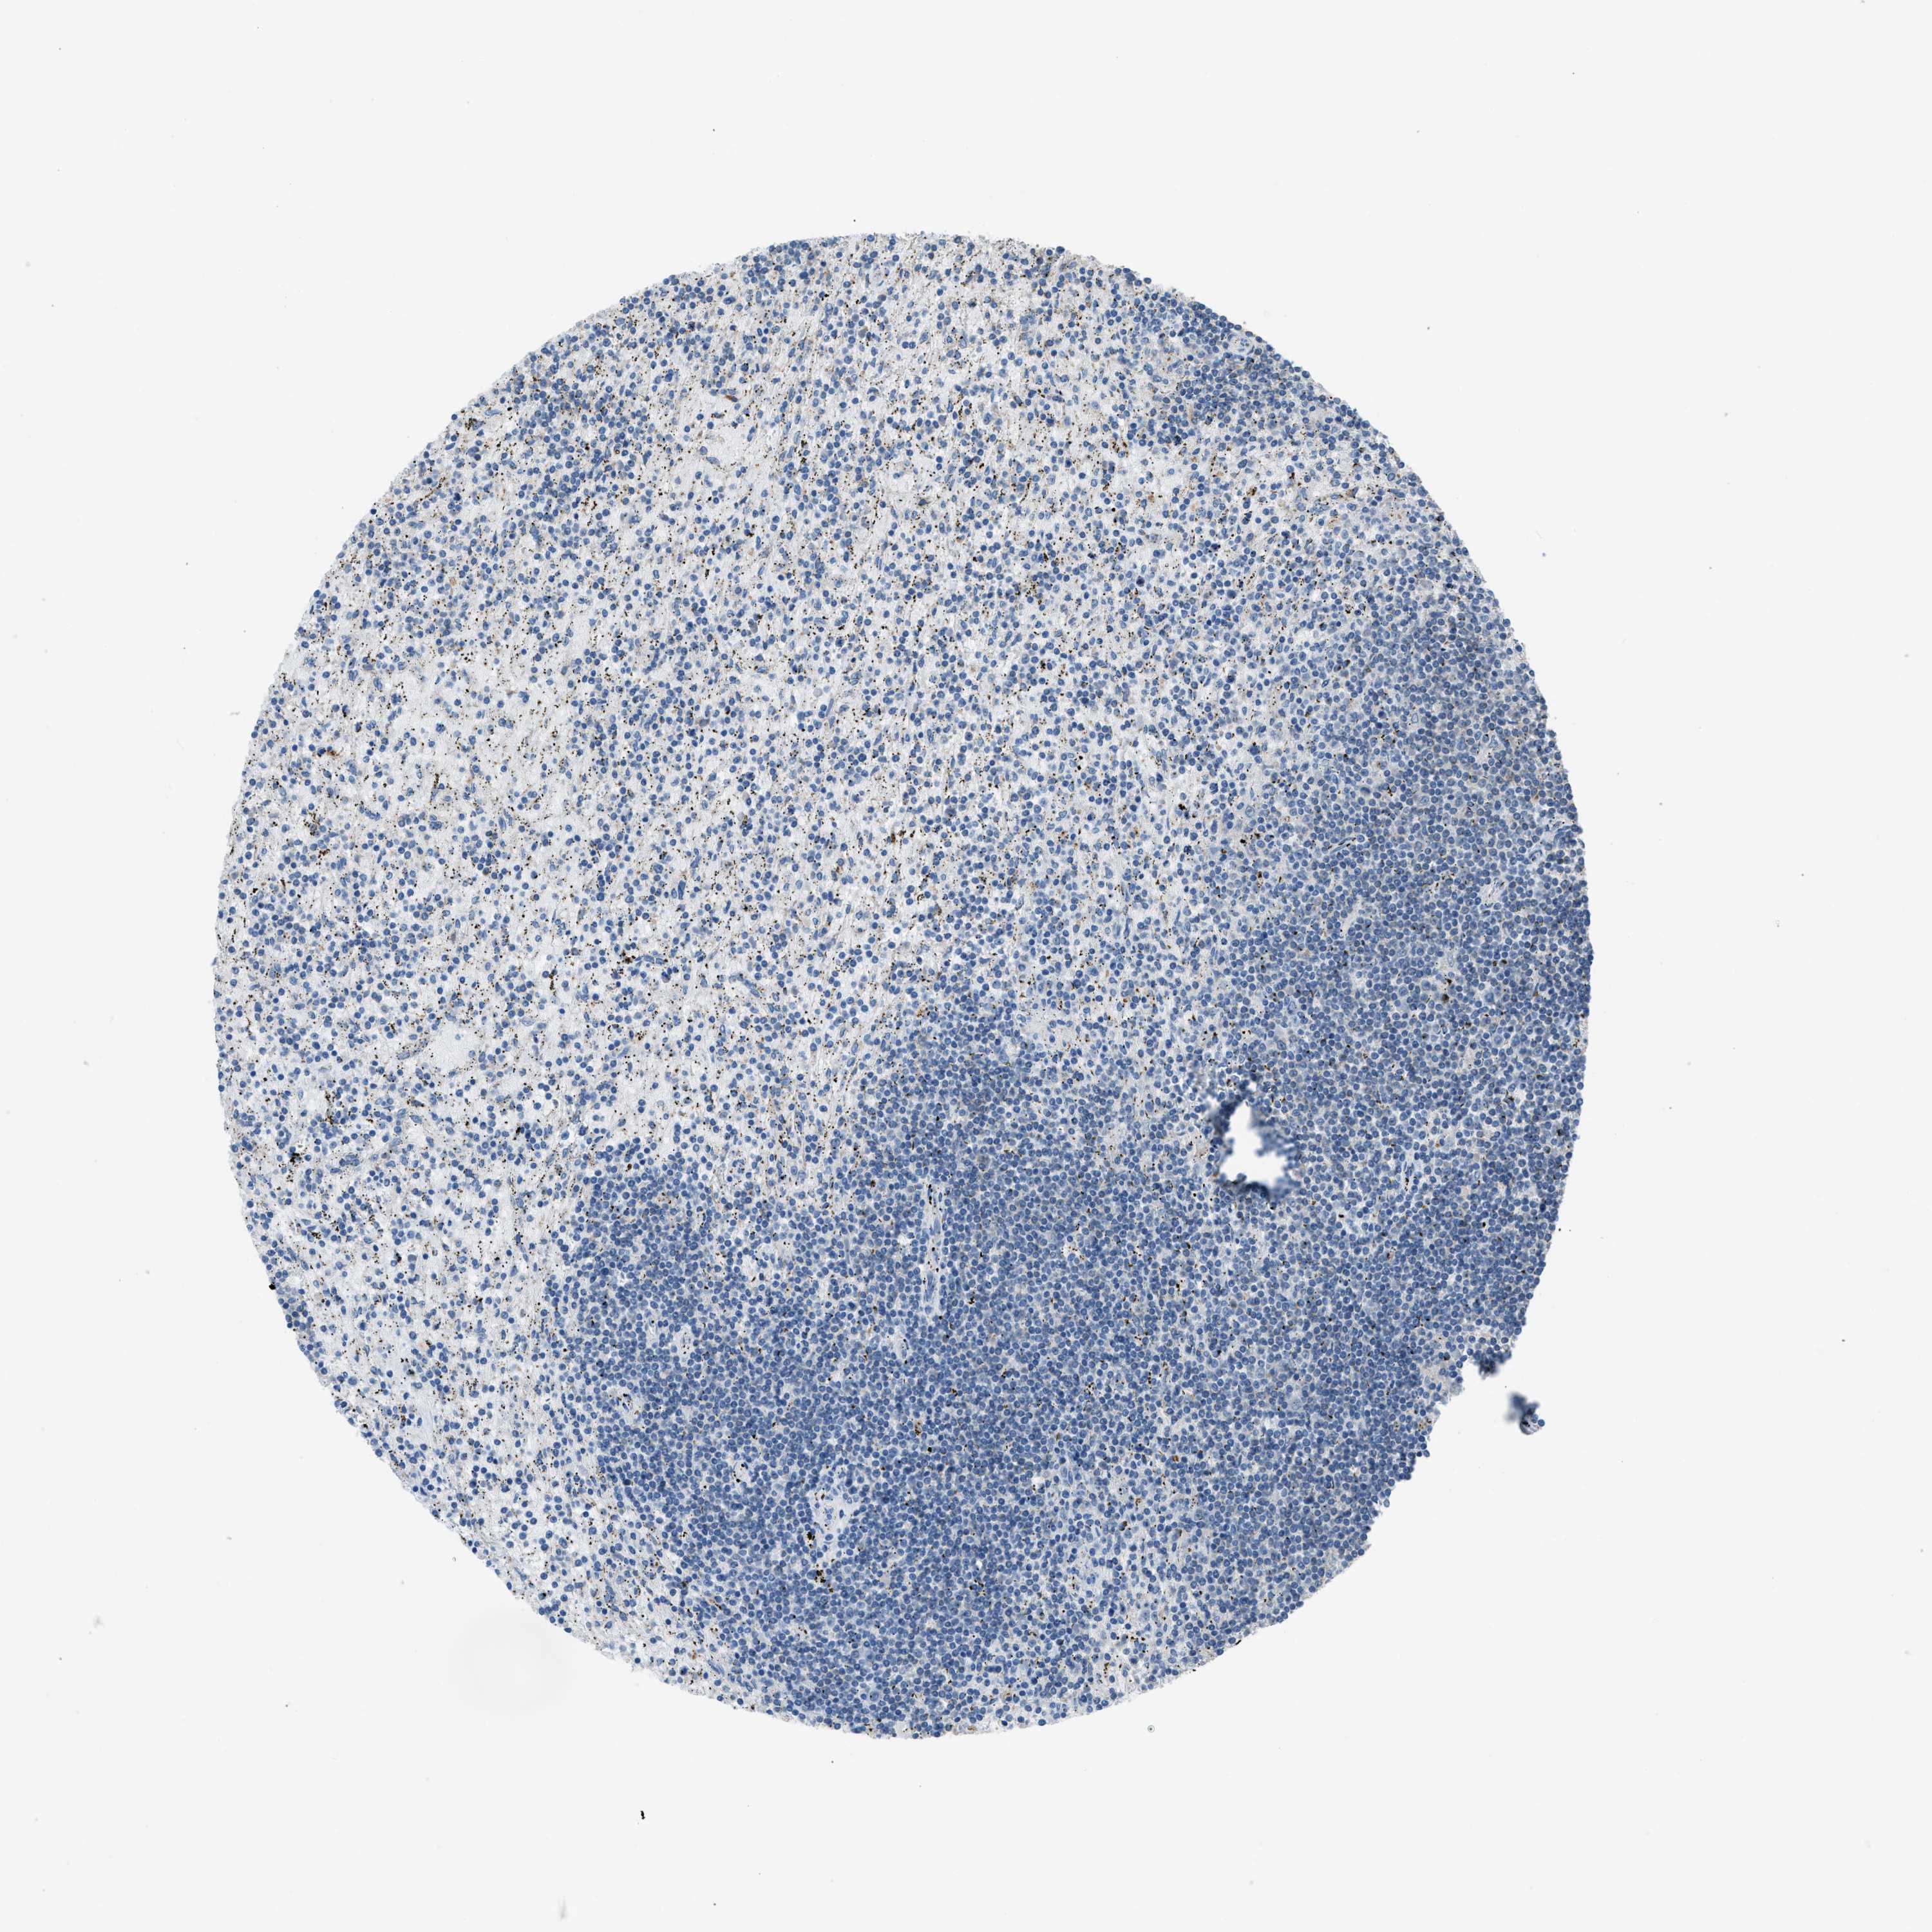

LYMPHOMA - Protein expressioni

A mouse-over function shows sample information and annotation data. Click on an image to view it in a full screen mode. Samples can be filtered based on level of antibody staining by selecting one or several of the following categories: high, medium, low and not detected. The assay and annotation is described here.

Antibody stainingi

Antibody staining in the annotated cell types in the current human tissue is reported as not detected, low, medium, or high, based on conventional immunohistochemistry profiling in selected tissues. This score is based on the combination of the staining intensity and fraction of stained cells.

Each image is clickable and will lead to virtual microscopy that enables deeper exploration of all samples and also displays staining intensity scores, fraction scores and subcellular localization as well as patient and tissue information for each sample.

Antibody HPA016552

Staining

High

Medium

Low

Not detected

Intensity

Strong

Moderate

Weak

Negative

Quantity

>75%

75%-25%

<25%

None

Location

Nuclear

Cytoplasmic/membranous

Cytoplasmic/membranous,nuclear

Hodgkin's disease, NOS

Malignant lymphoma, non-Hodgkin's type, High grade

Malignant lymphoma, non-Hodgkin's type, Low grade